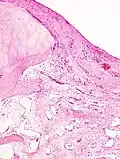

Histopathology of osteoarthrosis of a knee joint in an elderly female -